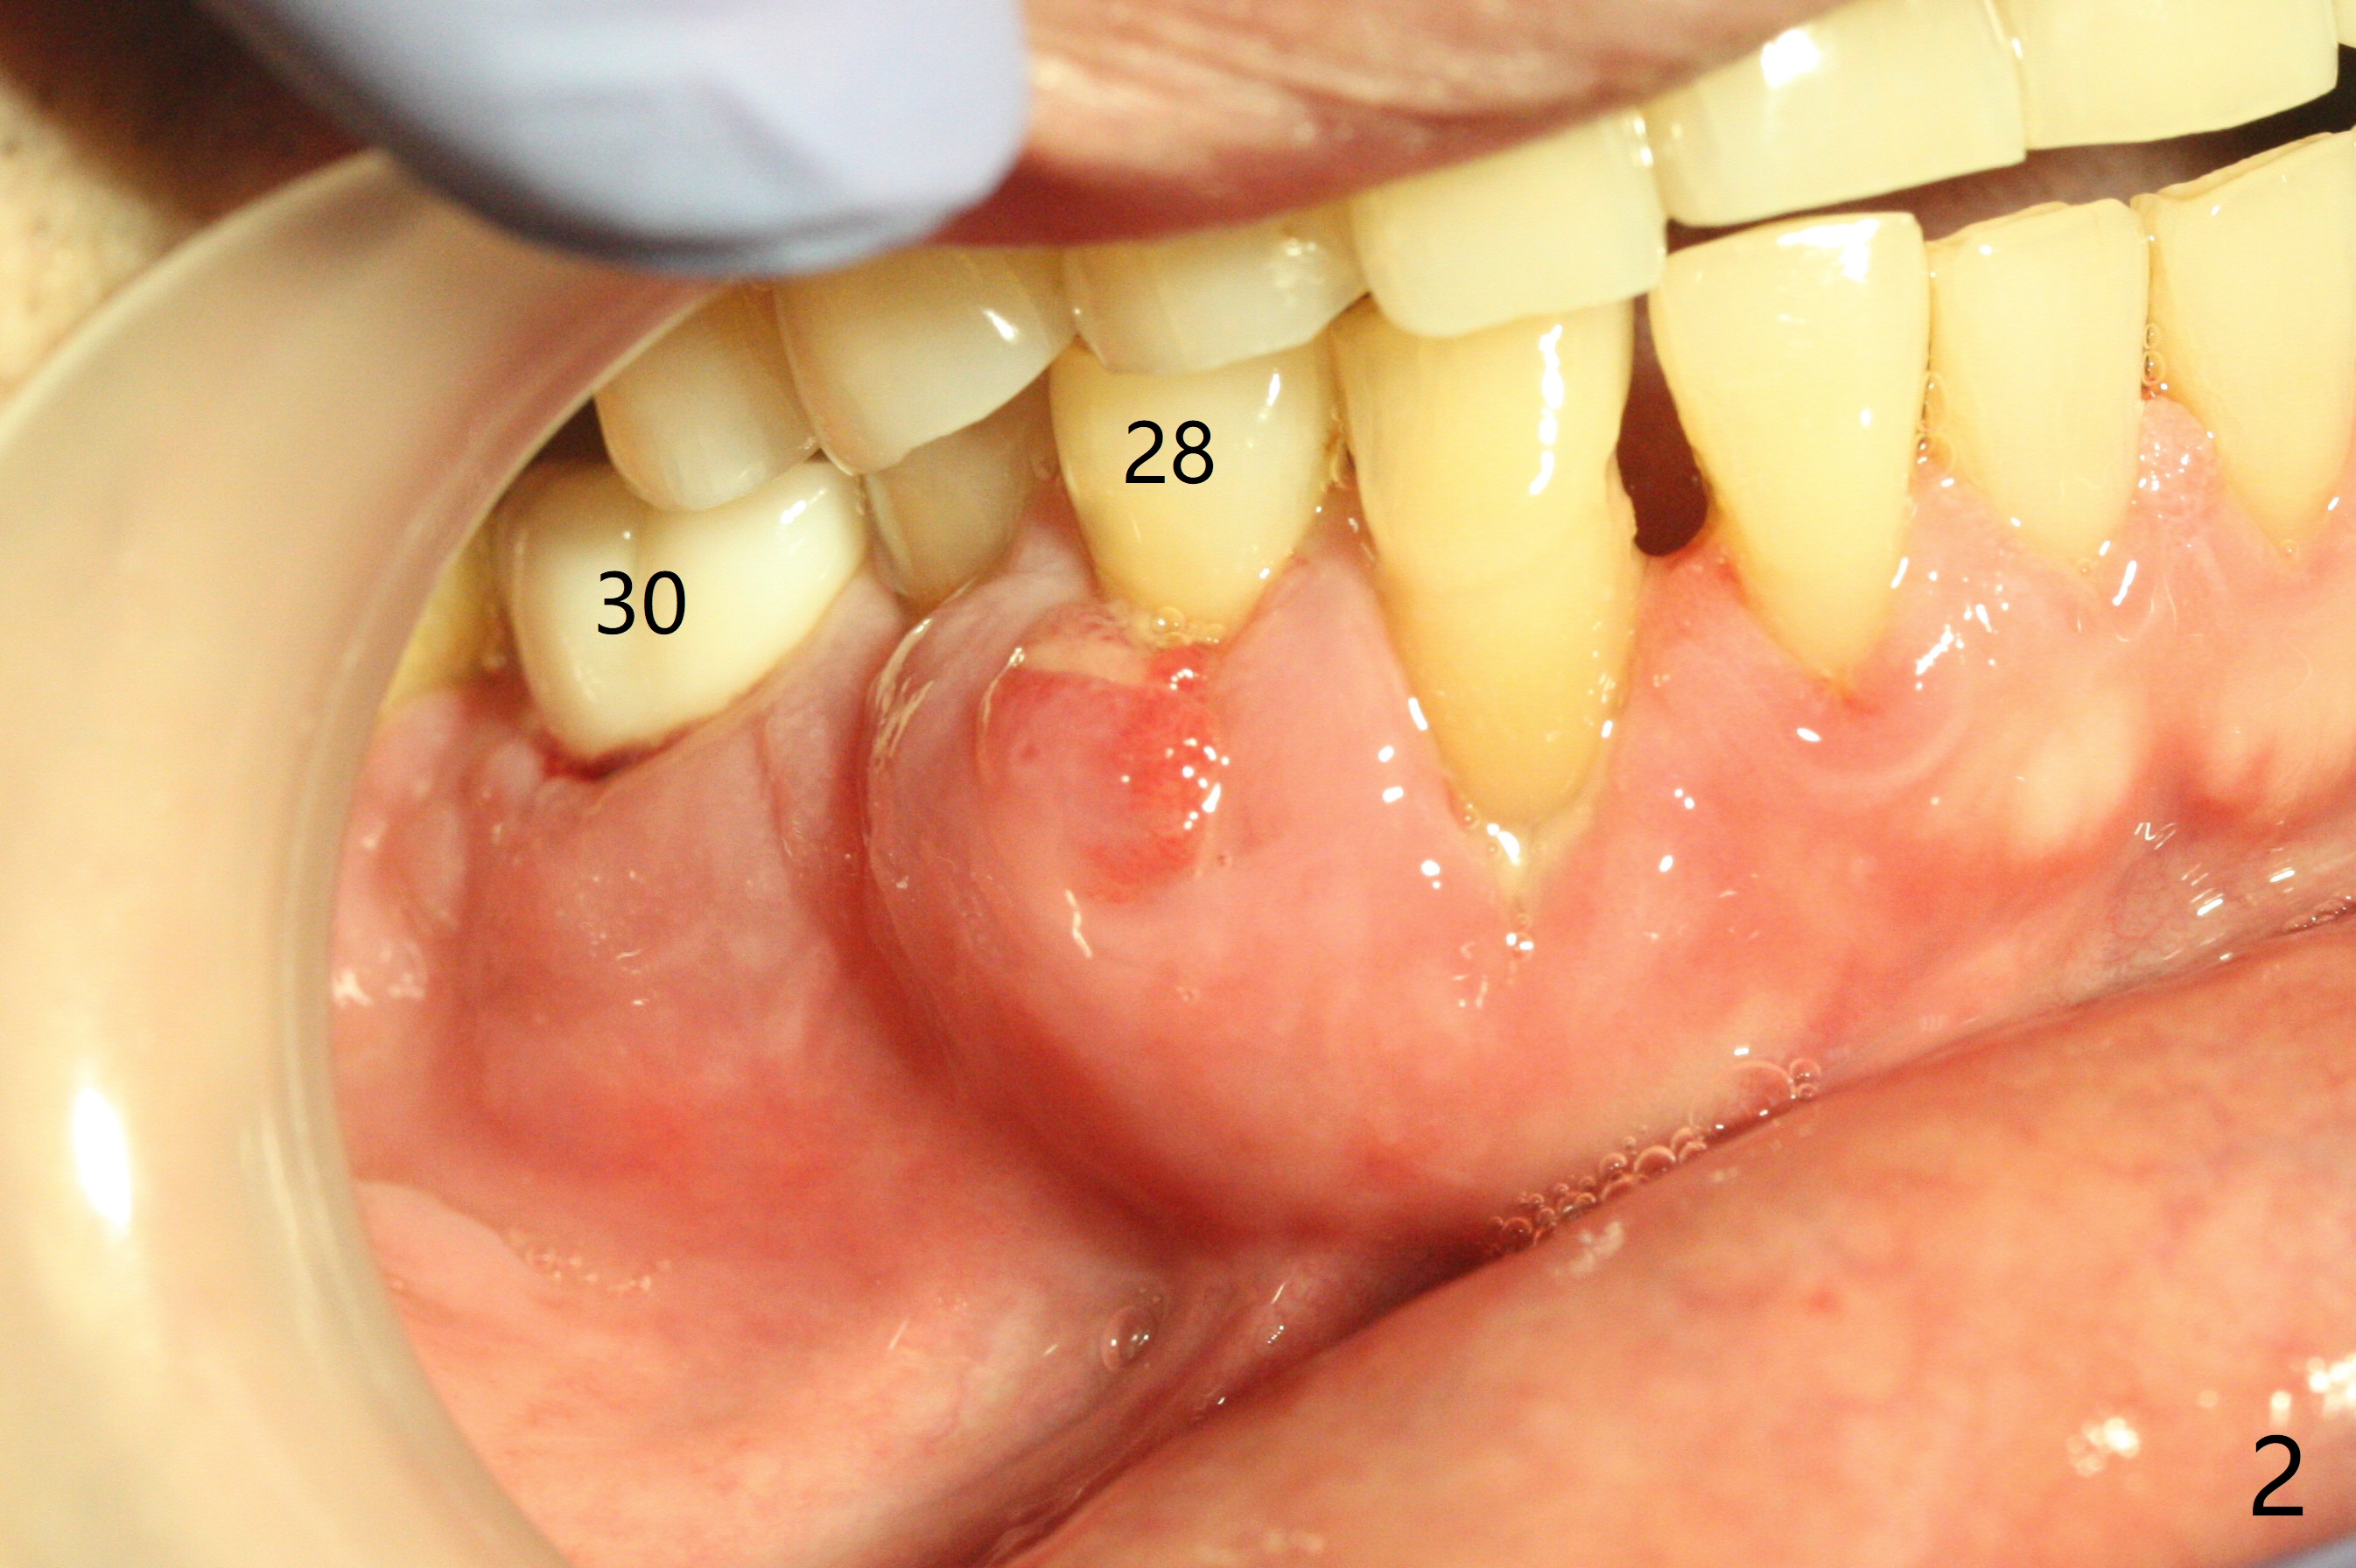

A 67-year-old man returns for periodic exam and #19 impression (Fig.3), which is impossible because there is open bite on the left (Fig.1 *). The latter is related to several periodontal abscesses (supraeruption, Fig.1,2). His chief complaint is mobility of #31 (Fig.3,4). Due to severity of infection, #31 is extracted with bone graft retained by Titanium-Reinforced Membrane (Cytoplast, Fig.5 T). PTFE suture is used. It is easy to tie knots with this non-resorbable (absorbable) suture. The Titanium-Reinforced Membrane exposes 1.5 months postop (Fig.6), which makes its removal easy (Fig.7). In fact the patient is pre-diabetic.